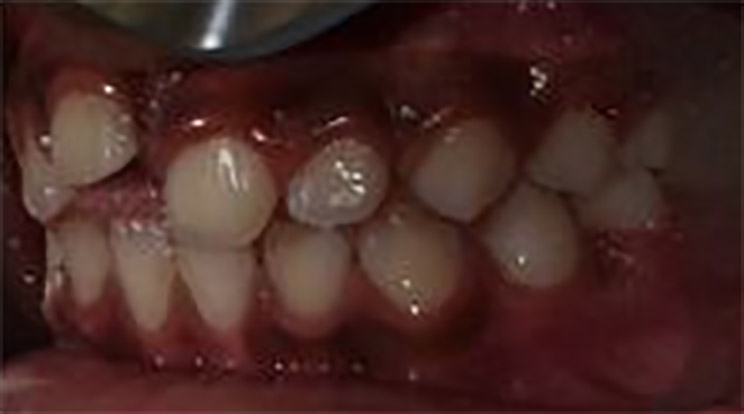

- Non-erupted tooth #8 and missing tooth #T

- Partially Erupted Teeth #6 and #11.

Cavitated lesions on teeth:#3-O #A-OBL,#14-O #19-O,#L-O, #S-O,and #30-OB

Figures 4,5 & 6: Posterior right, anteriors, and posterior left